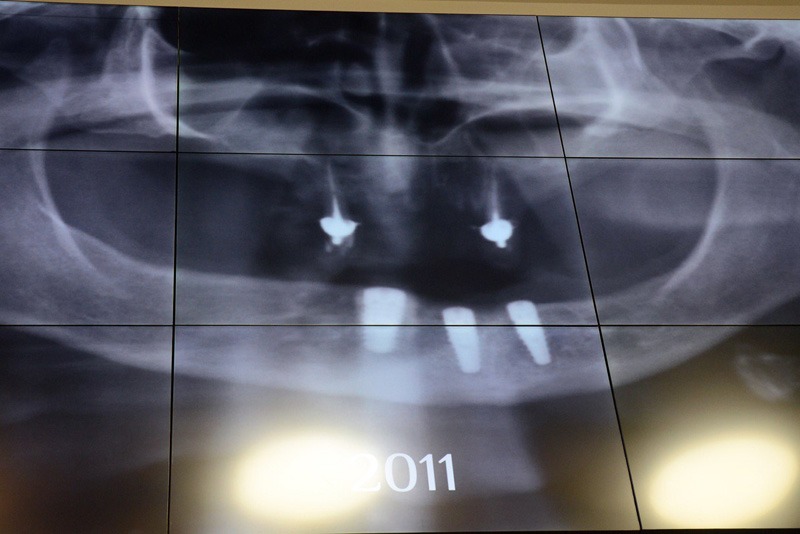

У першому блоці увагу було зосереджено на етапі планування як основі успішного результату. Лектор детально розкрив питання рентгенологічної діагностики та аналізу, пояснив концепцію ортопедичнокерованої імплантації. Окремо обговорювалися оптимальна кількість імплантатів для верхньої та нижньої щелеп, а також критерії вибору між знімними та незнімними конструкціями залежно від клінічної ситуації.